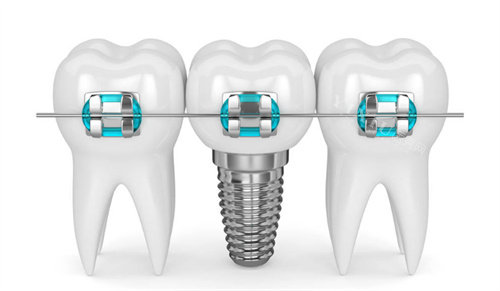

在追求健康美丽笑容的道路上,牙齿矫正成为了许多人的选择。而固定矫治器作为牙齿矫正中常用的工具,你对它的种类了解多少呢?接下来,让我们一起深入探究固定矫治器的不同类型,为你的牙齿矫正之旅提供参考。

金属托槽矫治器:经典耐用之选

金属托槽矫治器是更常见的一种固定矫正器,它由金属制成,通过粘在牙齿上的托槽和弓丝来施加力量,从而矫正牙齿。这种矫治器的优点十分明显,它价格相对便宜,而且耐用度高,对于比较复杂的牙齿问题也能有较好的矫正结果。

自锁托槽矫治器在托槽的设计上进行了改进,不需要用结扎丝固定弓丝,而是通过自锁装置直接将弓丝固定在托槽上。这种设计减少了摩擦力,提高了矫正效率,能让牙齿更快地移动到理想位置。同时,患者佩戴时的舒适度也有所提高,口腔内的附件相对较少,感觉更加舒适。